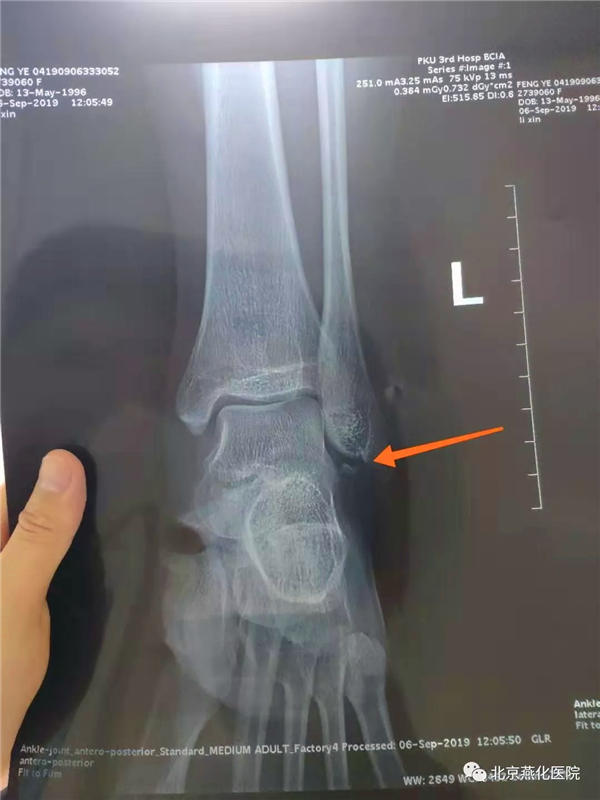

50多天之前,23岁的冯女士在北京首都机场候机时,被奔跑着的人拉着的行李箱不小心撞倒,从行李箱上面侧翻过去,摔倒在地。后被急救车送到医院,经X光片结合CT检查,显示左脚踝关节撕脱性骨折且左脚踝关节韧带损伤。2019年9月6日于外院进行石膏固定,后回家观察修养。在家卧床修养45天后复查,显示骨折痊愈,但拆除石膏后,冯女士下地走路时却仍感到疼痛,站立不稳。于是便乘坐轮椅来到北京燕化医院康复医学科进行康复治疗。